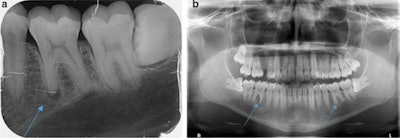

A healthy 28-year-old man with apical periodontitis on tooth #36 and #46 was referred by his primary dentist to the dental clinic at Saarland University. Though endodontic treatment had already begun, apical osteolysis was increasing on both teeth, according to the case report.

Upon examining the teeth, the dentist observed increased tooth mobility and bifurcation at a probing depth of 4 mm. The periodontal screening index was unremarkable, showing no signs of periodontal disease. However, tooth #36 and #46 each showed a 10-mm pocket with bleeding on probing at the vestibular central, and there was some bulging elastic swelling at the vestibulum, they wrote.

A percussion test was negative, and the exam and imaging revealed no anomalies, pulp calcifications, or formation defects of the hard tooth tissue. Also, there was no external resorption, root canal, or pulp chamber perforation, according to the report.

Then, two and a half months later, the patient's pain returned, prompting his primary dentist to take a new x-ray. This dentist diagnosed him with apical periodontitis on tooth #36 and #46, and he began endodontic treatment even though the teeth already appeared dead, the authors wrote.